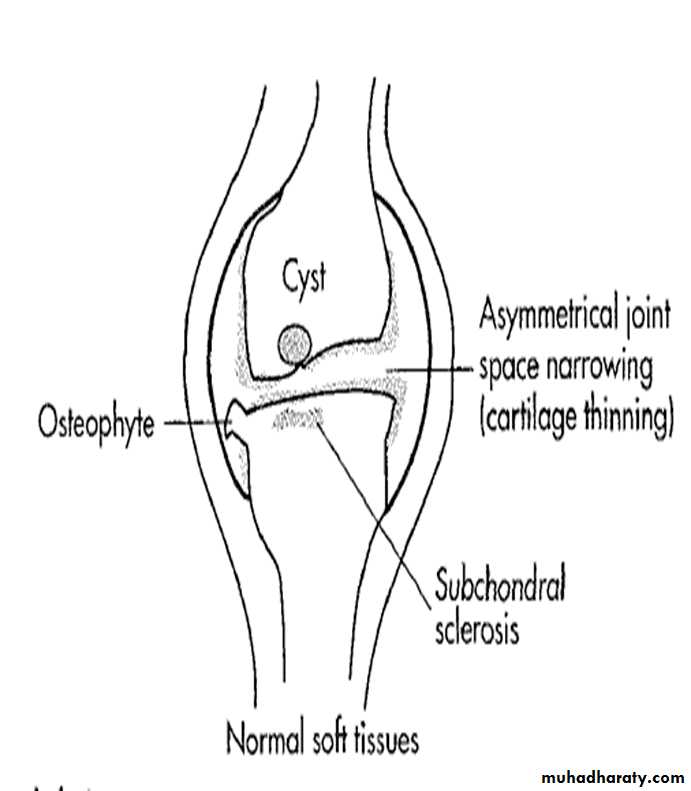

Radiographic features:

Five hallmarks:

* Narrowing of joint space, usually asymmetrical

*Subchondral sclerosis

* Subchondral cysts (true cysts or pseudocysts)

* Osteophytes

* Lack of osteoporosis